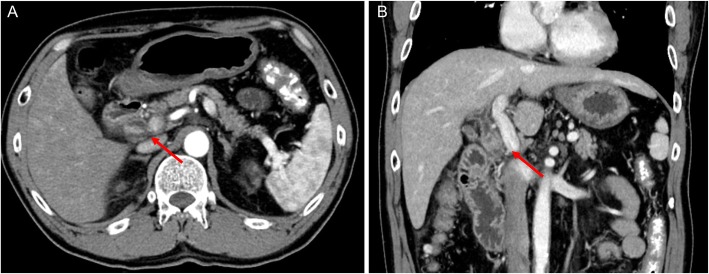

A 64-year-old man presented to our hospital with upper abdominal pain, jaundice, and anorexia. He had diabetes and was a social drinker but a lifetime non-smoker. Computed tomography (CT) scan revealed a dilated CBD, and acute cholangitis was suspected. The patient was referred to our hospital and admitted to the gastroenterology department for further investigation and treatment. Initial laboratory examinations revealed a white blood count (WBC) of 9770/μL, hemoglobin of 12.4 g/dl, increased C-reactive protein (CRP) of 5.47 mg/dl, total bilirubin of 7.75 mg/dl, AST/ALT of 176/281 IU/L, alkaline phosphatase of 815 IU/L, and ɤ-GTP of 132 IU/L. The serum tumor markers carcinoembryonic antigen (CEA) was within the normal range at 2.6 ng/ml and cancer antigen 19–9 (CA19–9) was elevated at 1162 U/ml. Both hepatitis B surface antigen (HBsAg) and antibodies to hepatitis C virus (anti-HCV) were negative. A plain CT scan on admission showed a high-density accumulation spreading throughout the CBD, and the entire CBD was dilated (Fig. 1). Gastroenterologists performed endoscopic retrograde cholangiopancreatography (ERCP) and endoscopic sphincterotomy (EST), during which a hematoma in the CBD was discovered. This revealed the reason for obstructive jaundice was not choledocholithiasis but the hematoma, which was subsequently drained through the incised Vater’s papilla (Fig. 2). A few days later, enhanced CT scan and magnetic resonance cholangiopancreatography (MRCP) were performed, and they showed improved dilation of the CBD and enhanced wall thickness of the bile duct measuring 25 × 10 mm at the union of the cystic and common hepatic ducts (Figs. 3 and 4). A cholangioscope detected an elevated tumor covered by sludge in the CBD (Fig. 5). The mucous membrane around the tumor showed redness and a malignant tumor was suspected. The result of the tumor biopsy revealed no malignant features in the histology, but the possibility of CC could not be denied from the macroscopic findings. We were consulted for surgical resection and performed an extrahepatic bile duct resection and cholecystectomy. Intraoperative rapid pathological diagnosis was performed, and we confirmed that the surgical margins in both the pancreatic and hepatic sides were cancer-free. The postoperative course was uneventful. The resected tumor had irregular elevated mucosa with an ulcerated lesion (Fig. 6a). The pathological examination of the resected tumor revealed that the ulcerated lesion had inflammatory granulation tissue; however, it did not contain the components of invasive carcinoma (Fig. 6b). Many consecutive intraepithelial micropapillary lesions spread around the ulcerated lesion, and the epithelial cells showed increased nucleus-to-cytoplasm ratio, nuclear hyperchromasia, and architectural atypia (Fig. 6c). The pathological diagnosis was BilIN-1 to -2. It also revealed that the BilIN-1 lesion spread through both the pancreatic and hepatic margins. Immunohistochemical staining showed that S100P was slightly expressed in the cytoplasm and MUC5AC was positive, while MUC1 was negative and p53 was not overexpressed (Fig. 6d–g).